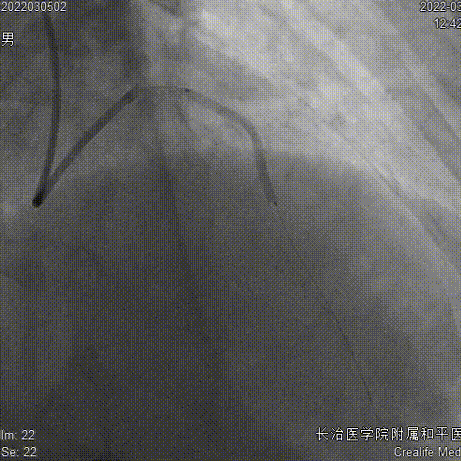

6FEBU3.5Guiding、Runthrough导丝、Sion导丝、2.0x15mm球囊

2.5x10mm切割球囊

药物球囊2.75x35mm、Telescope™导引延长导管

药物球囊定位、释放